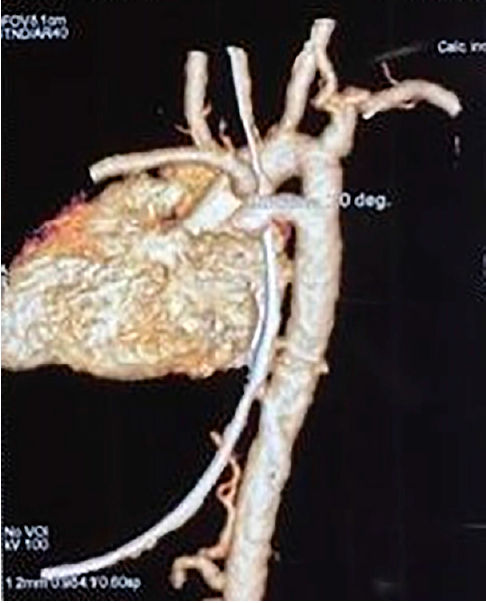

Figure 2.- Arteriografía de reconstrucción por Tomografía computarizada.

La arteriografía de reconstrucción por TC mostró que el arco aórtico derecho e izquierdo formaban un anillo vascular (Figura 6).

Figure 6.- Arteriografía de reconstrucción por tomografía computarizada. Arteriografía de reconstrucción por tomografía computarizada que muestra el arco aórtico derecho (círculo rojo) y el arco aórtico izquierdo (círculo verde) formando un anillo vascular.